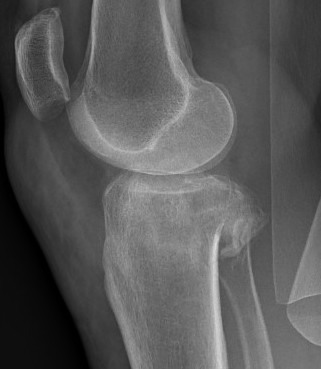

CT scan

Assess joint line

- predetermine fracture pattern before fixation

- will pick up medial condyle / bicondyle / metaphyseal fractures not seen on xray